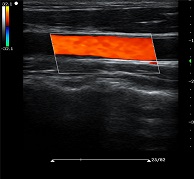

? ? ? ?C7為深圳安盛生物醫(yī)療技術(shù)有限公司新一代便攜式彩超產(chǎn)品,采用了先進(jìn)的PC平臺(tái),擁有強(qiáng)大的處理能力,優(yōu)異的圖像性能,集小巧輕便、全面的功能與輕巧流暢、特有的U型設(shè)計(jì)與一身,提供大眾新選擇。

? ?● 彩色多普勒增強(qiáng)技術(shù)

? ? ? ?有效抑制彩色血流閃動(dòng)噪聲,提高血流分辨率和靈敏度